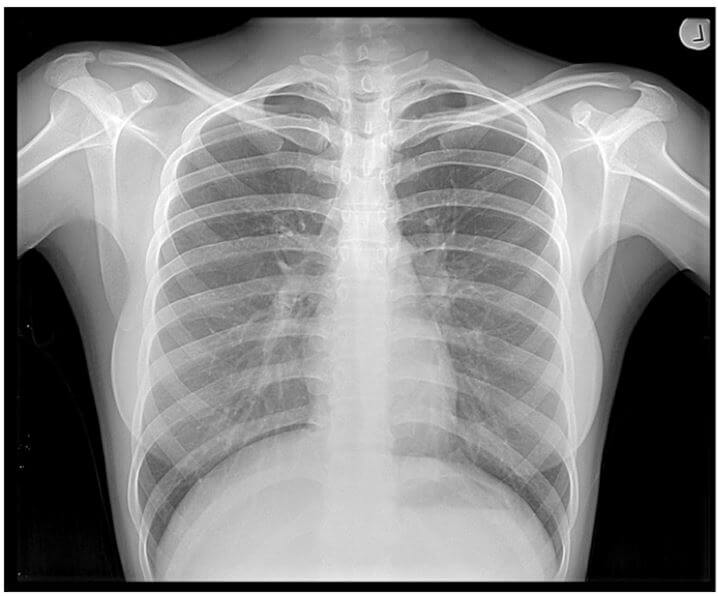

They “work” because it turns out that as they pass through the body, the energy from the X-rays is absorbed at different rates by different parts of the body. Dense parts of your body that X-rays find it more difficult to pass through, such as bone, show up as clear white areas on the image. Softer parts that X-rays can pass through more easily, such as your heart and lungs, show up as darker areas. Thus we get images like this, which we’ve all seen:

You need to know about them a) because clearly they can reveal things like broken bones (for example) which aren’t visible to the naked eye, and b) as with most forms of radiation, there is a health risk associated with exposure to them. That said, the part of your body being examined will only be exposed to a low level of radiation for a fraction of a second. For example, an X-ray of your chest, limbs or teeth is equivalent to a few days’ worth of naturally occurring background radiation, and has less than a 1 in 1,000,000 chance of causing cancer. If you would like further information, please check out this link on safe dosage levels.